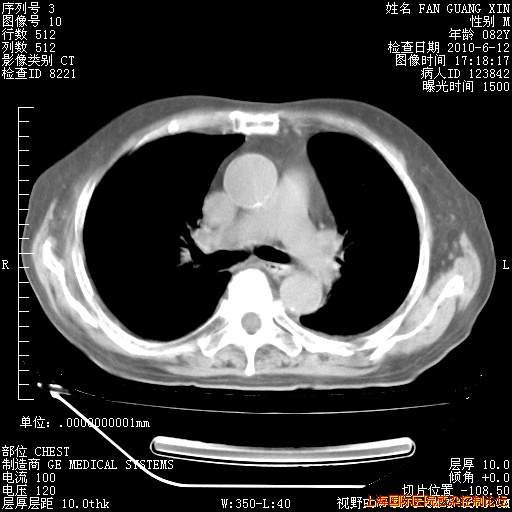

6月12日肺窗

回复

6月10日改甲强龙80mg qd ,在南京年会期间体温不稳,18日有一次寒战后体温达39度。19日开始用甲强龙60mg bid ,加量后第二天就不发热。本打算在两周后即7月3日减量,但是7月2日洗澡受凉、发热、咳嗽、鼻音,口服复方大青叶片,甲强龙120mg用到9日(整整20天)。

自昨天起甲强龙改为80mg qd。

在抗结核治疗2周后一般情况逐渐好转。